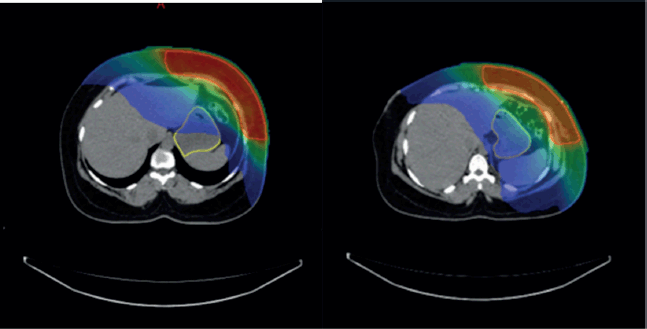

Overall, the significant factors influencing acute upper GI toxicity included radiation technique, RT dose and dose to stomach (D10 cc, D30 cc and D60 cc). Importantly, left chest wall or breast irradiation with or without RNI during FB was associated with a significantly higher risk of GI toxicity compared to DIBH, which holds a significant negative correlation implying a protective effect and helps in reducing GI toxicity (p = 0.035) (Supplementary

Figures 1a,b and 2a,b). Additionally, a positive correlation was found between larger PTV volume and the risk of developing acute upper GI toxicity (p = 0.036).

Supplementary Figure 1. (a and b): Axial CT scan showing stomach position in FB (VMAT Technique), Figure 3b: showing stomach position in DIBH (VMAT Technique).